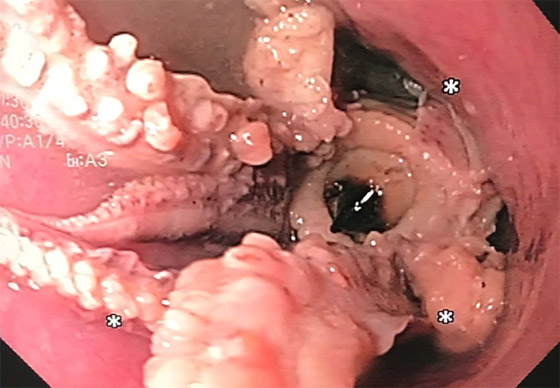

وشارك معهد الجمعية الأميركية للجهاز الهضمي (AGA) صورا مأخوذة من كاميرا المنظار الداخلي، وتُظهر المخلوق ذي المجسات الثمانية العالق في مريء الرجل. في البداية، جرب الأطباء "تقنية الدفع" ولكن سرعان ما اتضح أن الأخطبوط لن ينزل للأسفل، والضغط المفرط قد يؤدي إلى تمزق المريء. لذلك كان عليهم استخدام الملقط للإمساك بالمخلوق البحري وسحبه خارج المريء. وليس من الواضح لماذا ابتلع الرجل الأخطبوط كله، ولكن لحسن الحظ تعافى جيدا وخرج من المستشفى بعد يومين.

الأطباء ينقذون رجلا علق أخطبوط في حلقه! صورة رقم 3